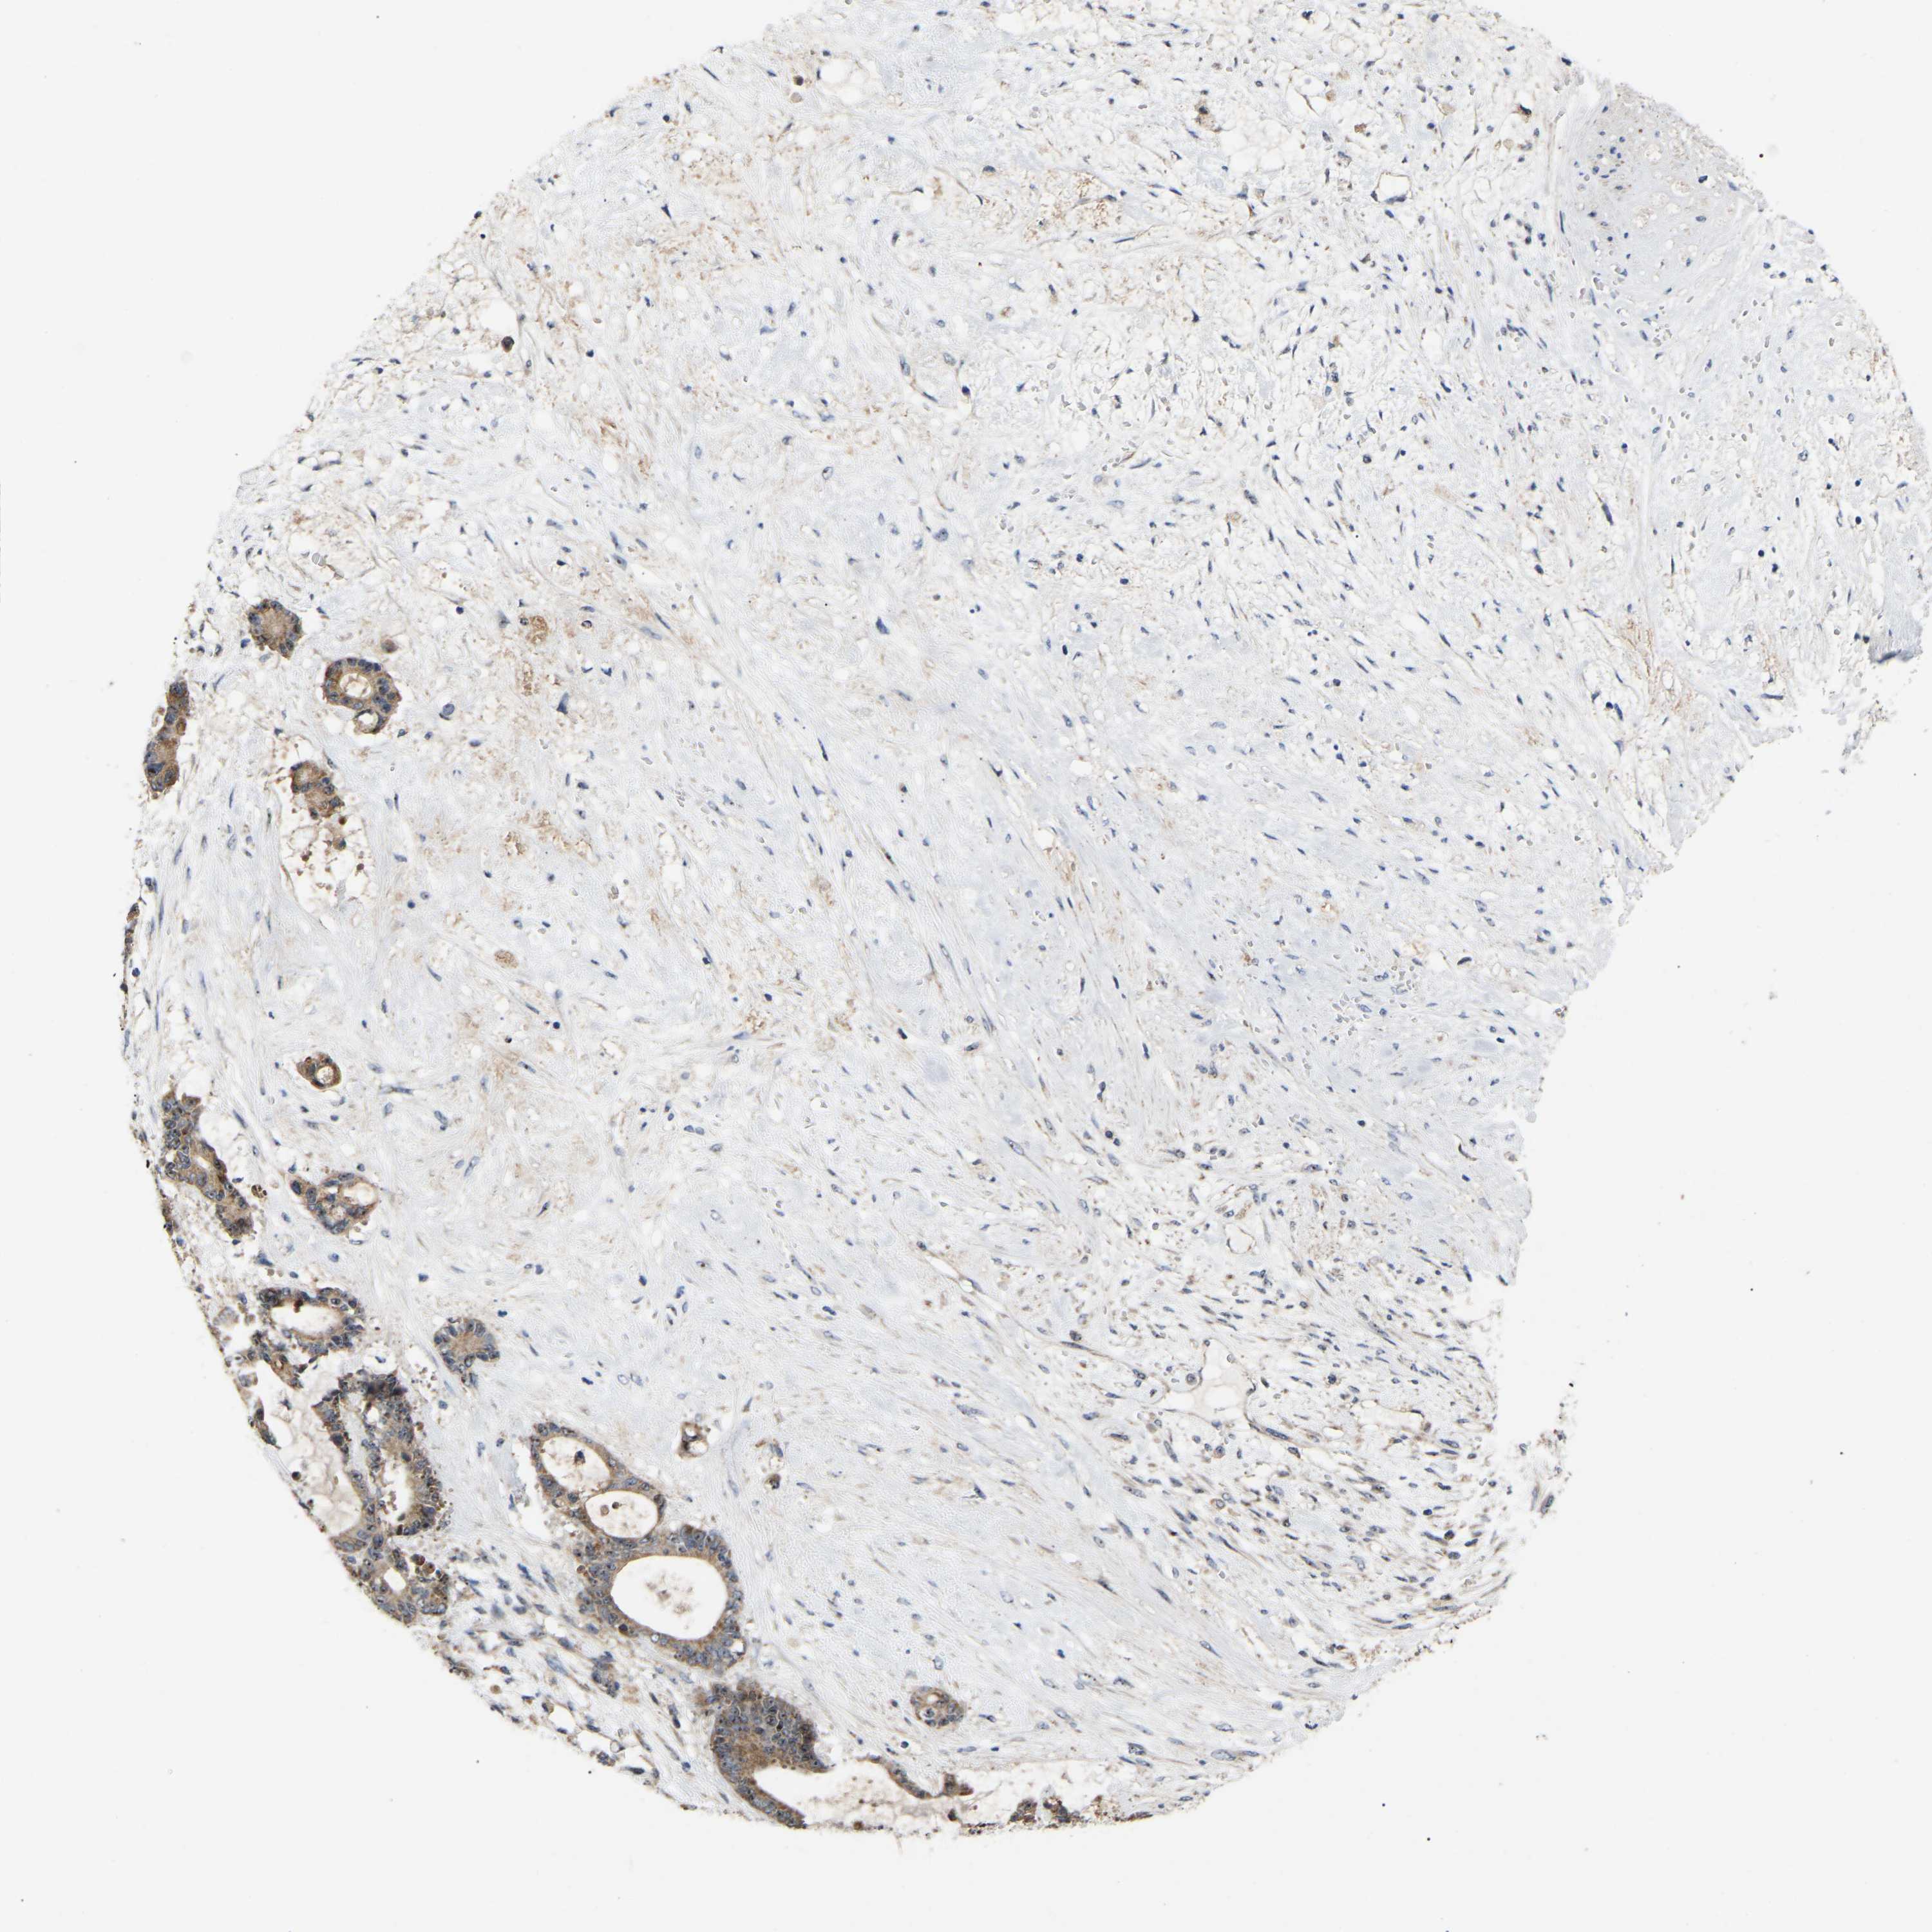

LIVER CANCER - Protein expressioni

A mouse-over function shows sample information and annotation data. Click on an image to view it in a full screen mode. Samples can be filtered based on level of antibody staining by selecting one or several of the following categories: high, medium, low and not detected. The assay and annotation is described here.

Note that samples used for immunohistochemistry by the Human Protein Atlas do not correspond to samples in the TCGA dataset.

Antibody stainingi

Antibody staining in the annotated cell types in the current human tissue is reported as not detected, low, medium, or high, based on conventional immunohistochemistry profiling in selected tissues. This score is based on the combination of the staining intensity and fraction of stained cells.

Each image is clickable and will lead to virtual microscopy that enables deeper exploration of all samples and also displays staining intensity scores, fraction scores and subcellular localization as well as patient and tissue information for each sample.

Antibody HPA018999

Staining

High

Medium

Low

Not detected

Intensity

Strong

Moderate

Weak

Negative

Quantity

>75%

75%-25%

<25%

None

Location

Nuclear

Cytoplasmic/membranous

Cytoplasmic/membranous,nuclear

Cholangiocarcinoma

Carcinoma, Hepatocellular, NOS